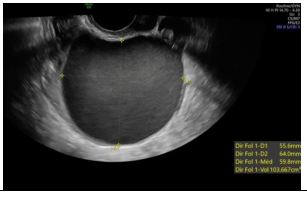

Paciente de 32 anos com infertilidade primaria há 3 anos, ciclos menstruais regulares, sem dispareunia, sem dismenorreia, realiza ultrassom transvaginal no 23 dia do ciclo menstrual, identificando a seguinte imagem anexial.

A imagem ecográfica sugere como diagnóstico